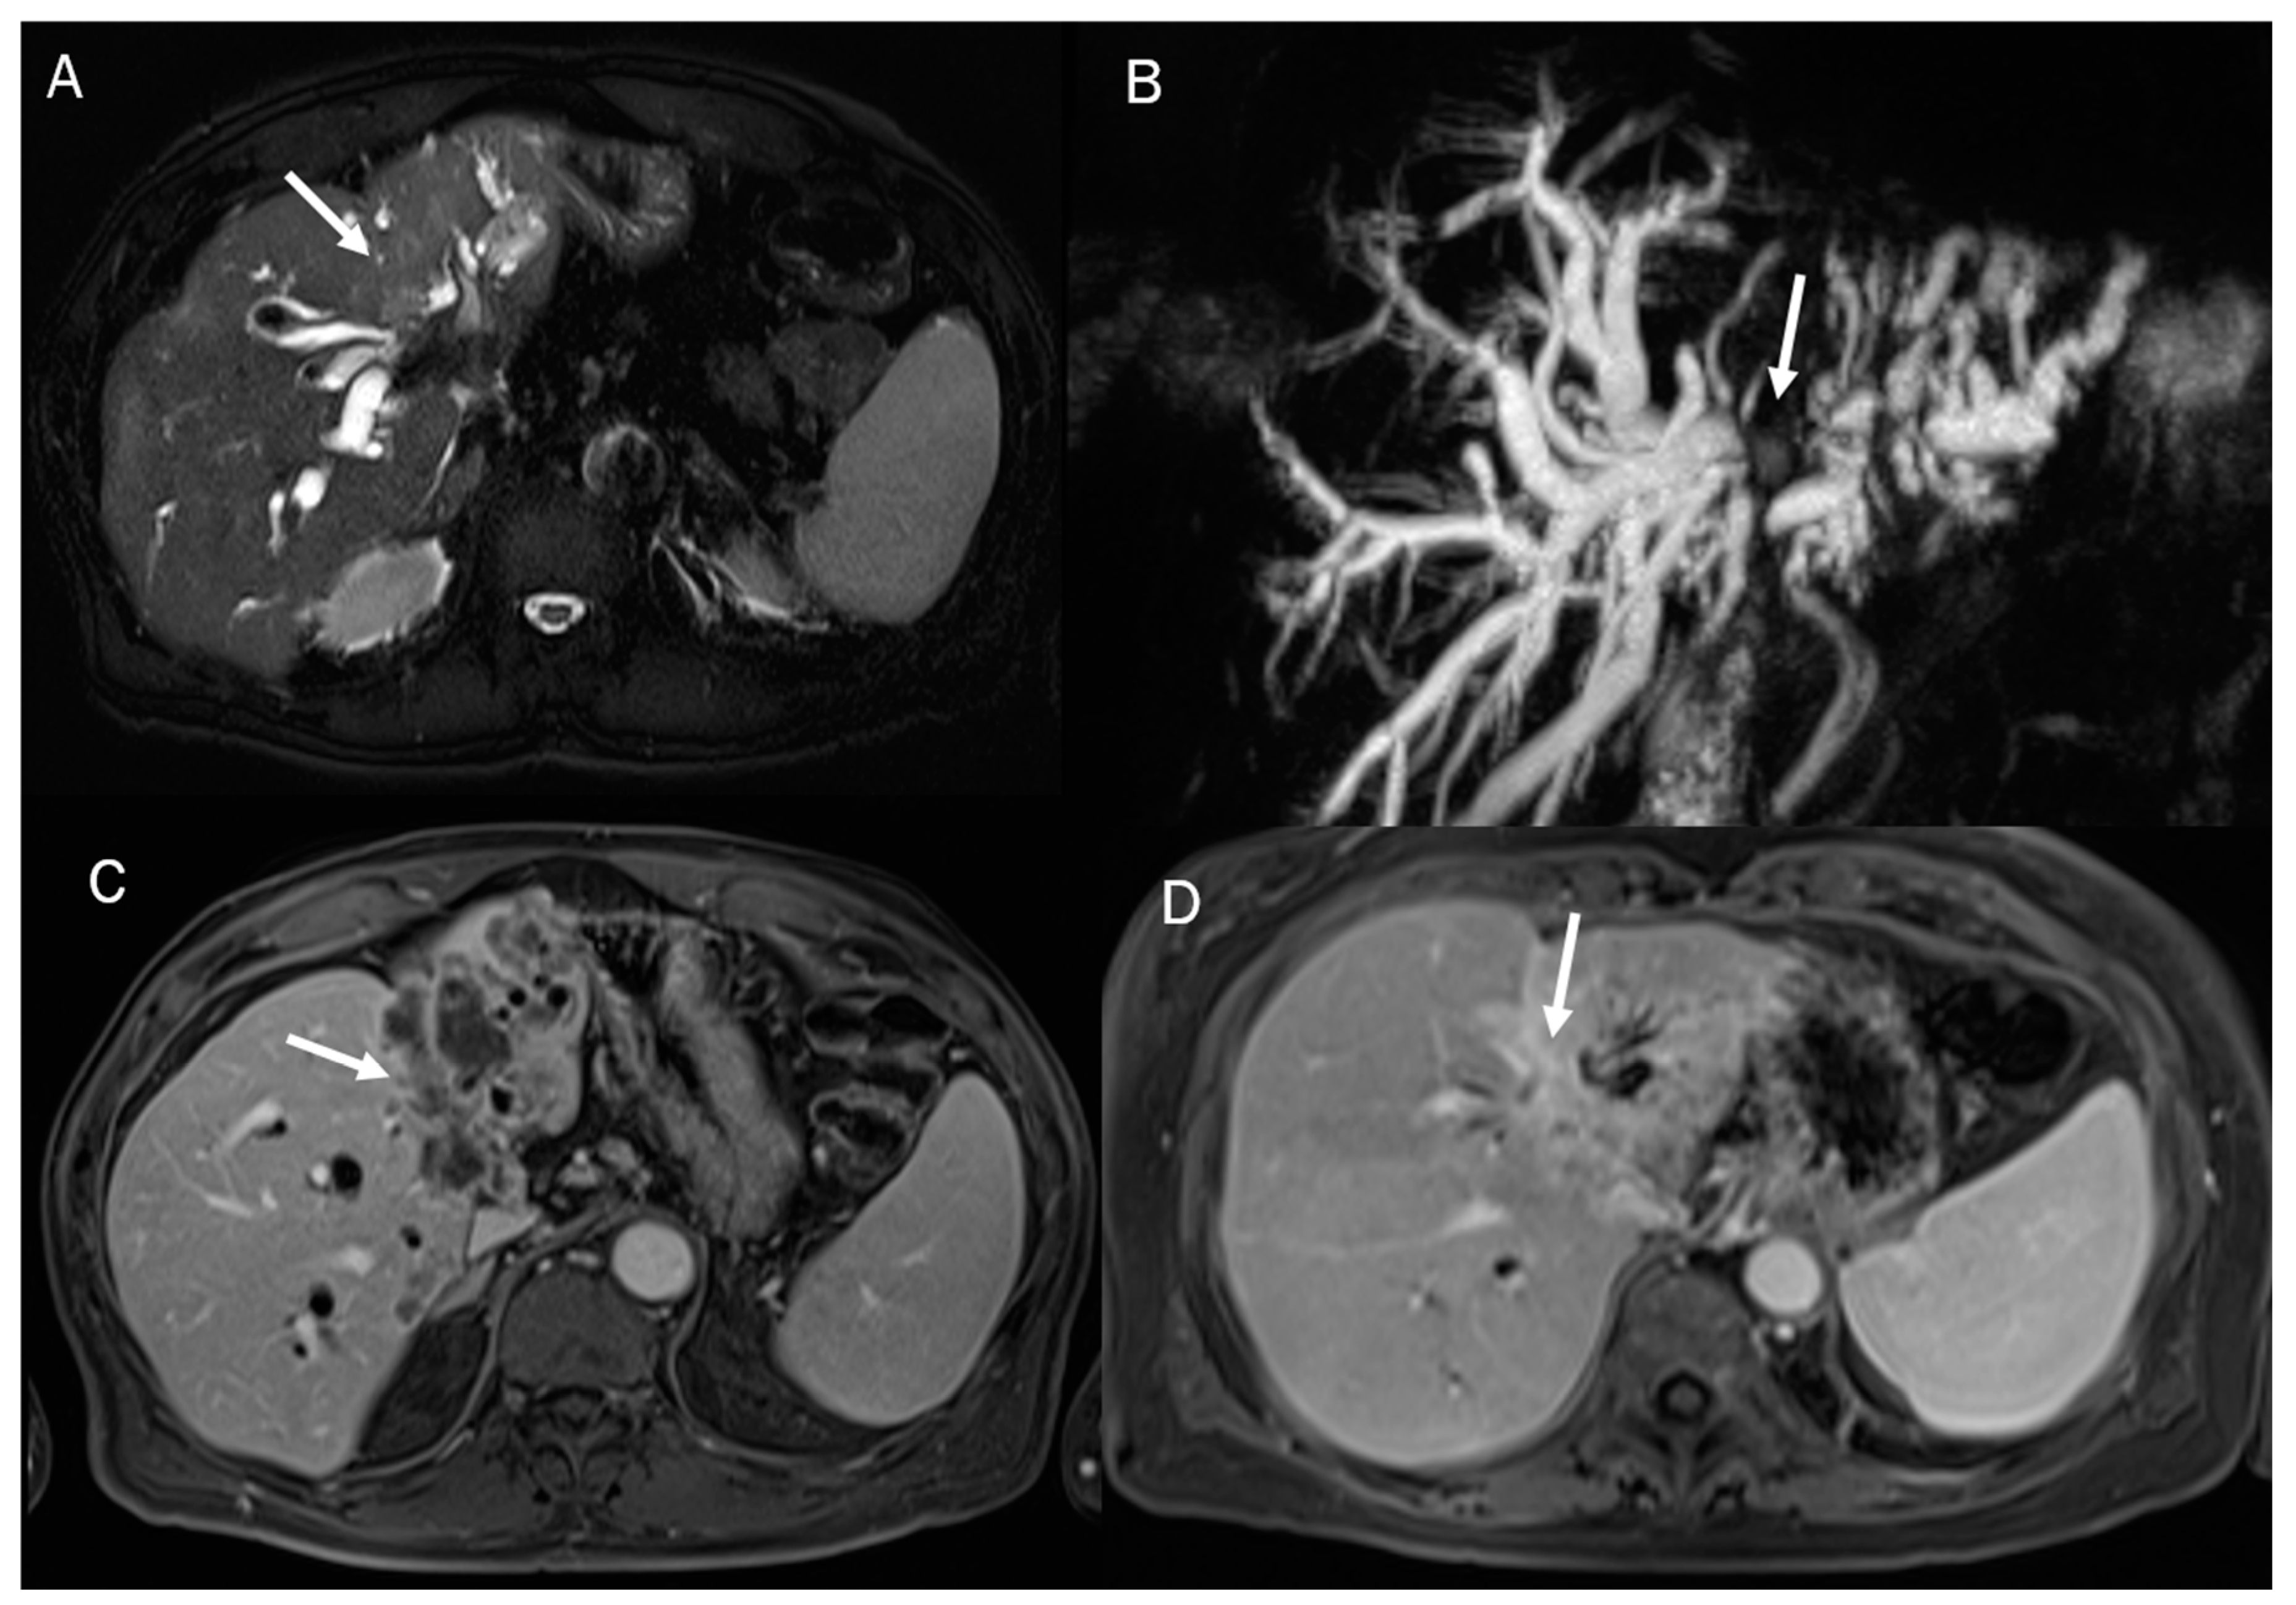

Figure 6.

MRI assessment of periductal-infiltrating CCA. The lesion (arrow) shows hyperintense signal in T2-W (A), causing biliary tree dilatation in cholangiography sequences (B). During arterial phase (C), the lesion causes hyperenhancement of surrounding liver parenchymal, showing a progressive contrast enhancement in portal phase (D).

In MRI imaging, ICC presents typical features as capsular retraction adjacent to the tumor. In T1-W sequences, the lesion appears with a targetoid aspect or hypointense signal. While most of the lesions also appear targetoid (Figure 5) in T2 sequences, some can show hyperintense signals. After contrast administration in the arterial phase in ICC, it is possible to identify the peripheral rim hyperenhanced. In the portal phase, the lesion slowly increases its entire enhancement (Figure 5 and Figure 6) [181,182,183,184].